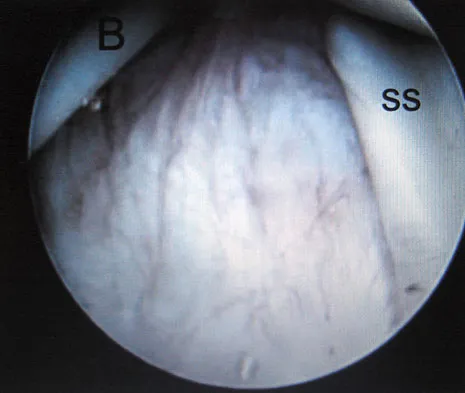

The MRI scan of the shoulder shown in Figure 2 was performed with the arm in abduction and external rotation. The image reveals what condition?

Explanation